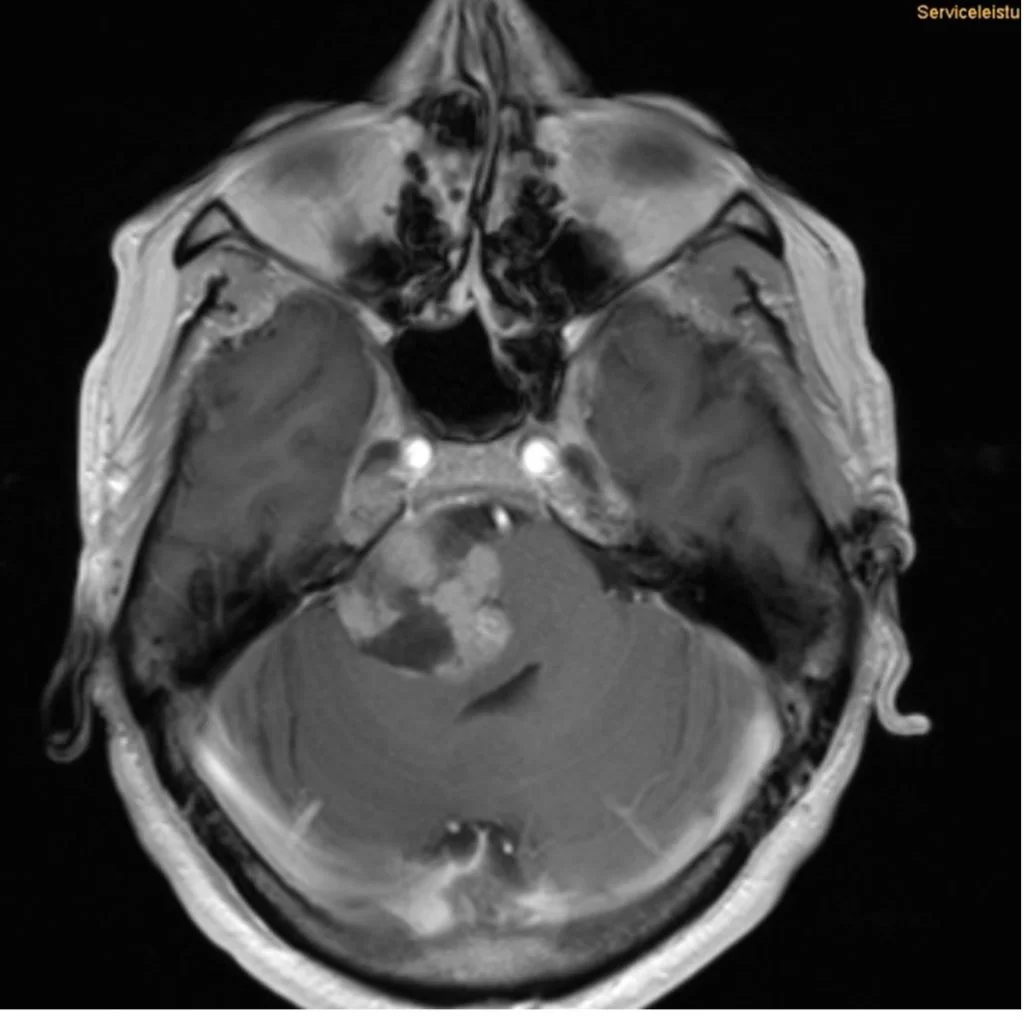

Ακουστικό Νευρίνωμα Δεξιά

Ασθενής γυναίκα 68 ετών με προοδευτική επιδείνωση της ακοής δεξιά και επεισόδια ιλίγγων και διαταραχής της ισορροπίας και βάδισης. Η